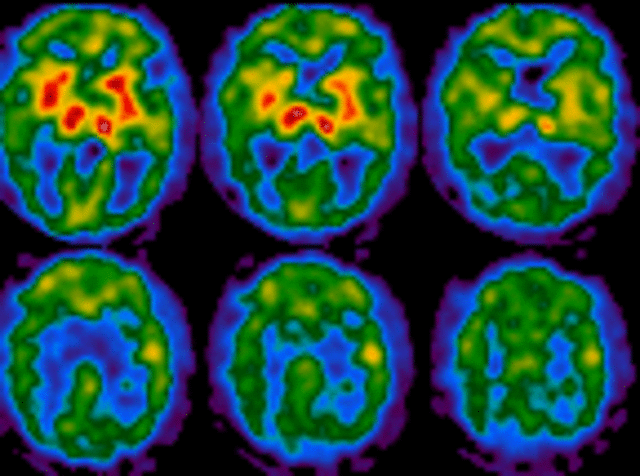

New Parkinson’s Disease Chemical Messenger Discovered – Neuroscience News

disease parkinson brain neurons parkinsons neurosciencenews discovery between discovered